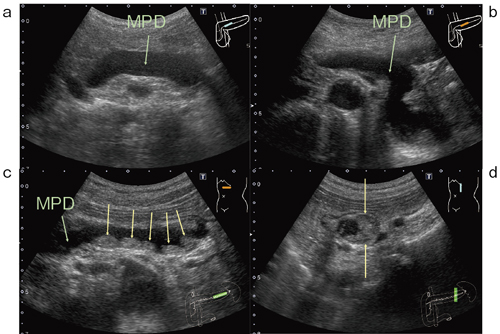

●症例3:膵管内乳頭粘液性腫瘍(IPMN,70歳代,女性)

IPMN(膵管内乳頭粘液性腫瘍)の症例である。主膵管は体部から尾部にかけて拡張しており,Bモード画像でも主膵管の尾側端に複数の乳頭状の腫瘤を確認でき,主膵管型IPMMと診断した(図6c↓)。短軸方向でみると内腔面が狭くなり,乳頭状の腫瘍が内腔に張り出していることがわかる(図6d↓)。

図6 症例3:膵管内乳頭粘液性腫瘍(IPMN)のBモード画像

MPD:主膵管